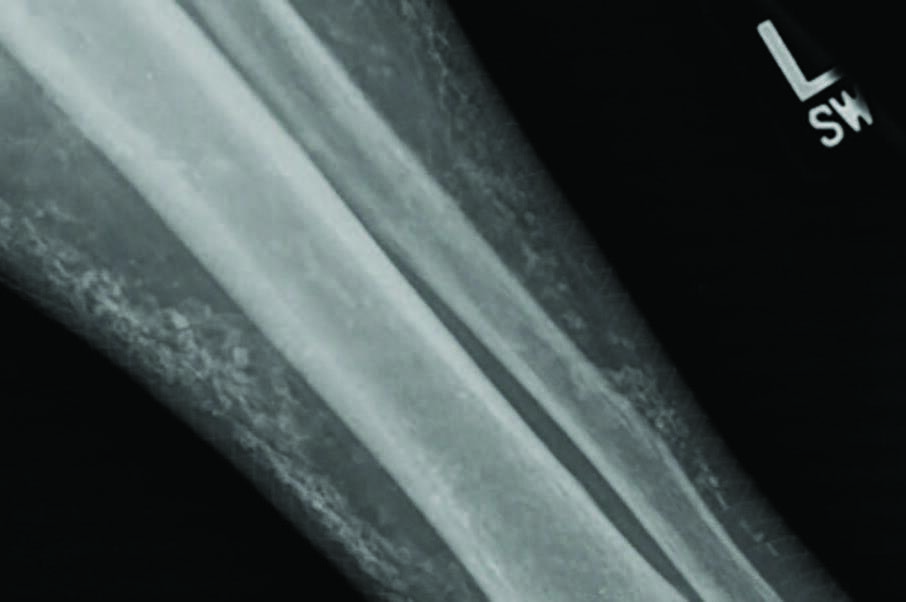

The orthopedist providing an additional opinion ordered radiographs, which showed multiple soft tissue calcifications along the anterior tibia and fibula with no evidence of cortical disruption (see second photo above). At this point, the orthopedist deferred further treatment to infectious disease, who attempted a six-week regimen of culture-driven IV antibiotics.

The final diagnosis was calcinosis cutis secondary to lipodermatosclerosis, especially given the patient’s history of chronic venous stasis and cutaneous changes. We prescribed oral colchicine 0.6mg daily (for its anti-inflammatory properties) and topical 25% sodium thiosulfate (for its calcium-chelating action1,2,4-6). The patient applied the sodium thiosulfate, mixed with zinc oxide paste in a 1:3 ratio, daily under a dry, sterile dressing. The patient saw drastic improvement in his ulcerations with near resolution of all open areas three months into therapy (see last photo above). Since then, the patient’s primary care physician recommended referral to vascular surgery for possible venous ablation.